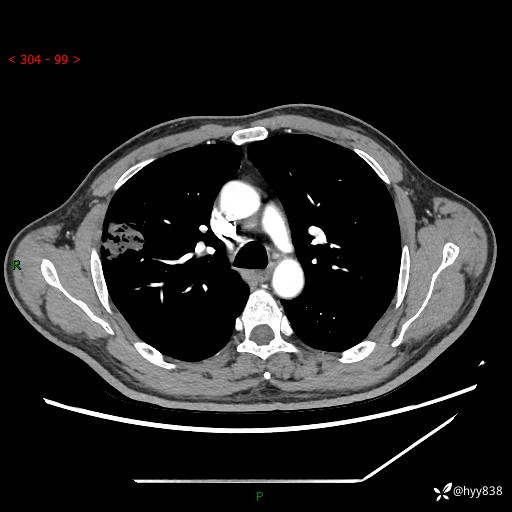

现病史:患者2天前体检完善胸部CT提示:右上肺团块影,炎症可能,肿瘤性病变不除外,冠状动脉钙化,无咳嗽、咳痰,无寒战发热,无恶心、呕吐等其他特殊不适,未予以特殊治疗,现为明确病变性质来我院就诊,门诊以“肺肿物性质待查”收入我科。 起病以来,患者精神、饮食、睡眠可,大小便正常,体力体重较前无明显变化。

胸部CT平扫+增强